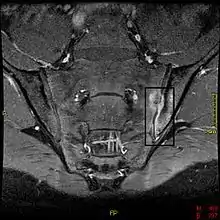

لا يوجد فحص مباشر يمكن إجرائه لتشخيص التهاب الفقار المقسِّط، ولكن يعد فحص Schober’s عند الفحص السريري من أهم الاساليب لقياس قدرة المريض على ثني المفاصل القطنية كما يستخدم هذا الفحص كوسيلة لقياس مدى تقدم الحالة المرضية واستجابتها للعلاج،[9] ويعتبر التصوير بالرنين المغناطيسيّ (MRI) والتصوير بالأشعة السينية (X-ray) اللذان يكشفان عن تغيرات أو التهابات في المفصل العجزيّ الحرقفيّ بالإضافة لفحص الدم للبحث عن واصم جيني، من أهم الادوات والأساليب مستخدمة عند التشخيص.

ويعتمد تشخيص المرض على أعراض المريض والفحص السريري. صور الأشعة السينية توضح آثار الالتهاب في المفصل العجزي الحرقفي مثل عدم وضوح الحدود المفصلية والتآكلات. أما الفحوصات المختبرية فتكون متماشية مع الصورة المختبرية للالتهابات كارتفاع في عدد كريات الدم البيضاء وزيدة في سرعة ترسب الكريات الحمراء (Erythrocyte Sedimentation Rate ESR) وزيادة في بروتين ج التفاعلي (C-reactive protein). فحص شوبر هو أحد الفحوصات السريرية المستخدمة في هذه الحلات، حيث يقيس هذا الفحص مدى قدرة المريض على ثني العمود الفقري. كما يستخدم هذا الفحص كوسيلة لقياس مدى تقدم الحالة المرضية واستجابتها للعلاج.

- التآكل والتصلّب في المفاصل العجزيّة الحرقفيّة هي أول التغيرات التي تظهر في صورة الأشعة السينية (X-ray).

- الاستمرار في التآكل يؤدي إلى ظهور توسّع كاذب في المسافات المفصلية وظهور قسطٌ عظميّ.

فترة متأخرة من بداية المرض الفعليّ عند المريض قد تصل من 8-10 سنوات حيث يتأخر بها التشخيص وتتأخر عملية المعالجة بالأدوية لذلك، يستخدم التصوير المقطعيّ المحوريّ المحوسب(tomography)، والتصوير بالرنين المغناطيسي (MRI) للمفاصل العجزيّة الحرقفيّة للتشخيص المبكر ولكن، مدى دقة هذه الأدوات ما زالت غير واضحة تماماً.